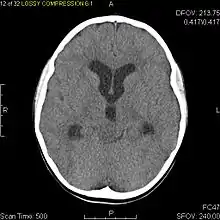

Diagnostic method | MRI, CT scan |

Usually – depending on the interview of the patient and after a clinical exam which includes a neurological exam and an ophthalmological exam – a CT scan and/or an MRI scan will be performed to confirm the presence of a tumor. They are usually easily distinguishable from normal brain structures using these imaging techniques. A special dye may be injected into a vein before these scans to provide contrast and make tumors easier to identify. Pilocytic astrocytomas are typically clearly visible on such scans, but it is often difficult to say based on imaging alone what type of tumor is present.